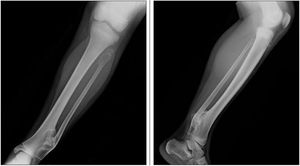

An apparently healthy 9-year-old girl noted to have left ankle mass during well-child checkup. Her last well-child visit was 3 years earlier. Medical history unremarkable. She denied fevers, weight loss, night sweats, and chills. No family history of bone deformities or growth disturbances.